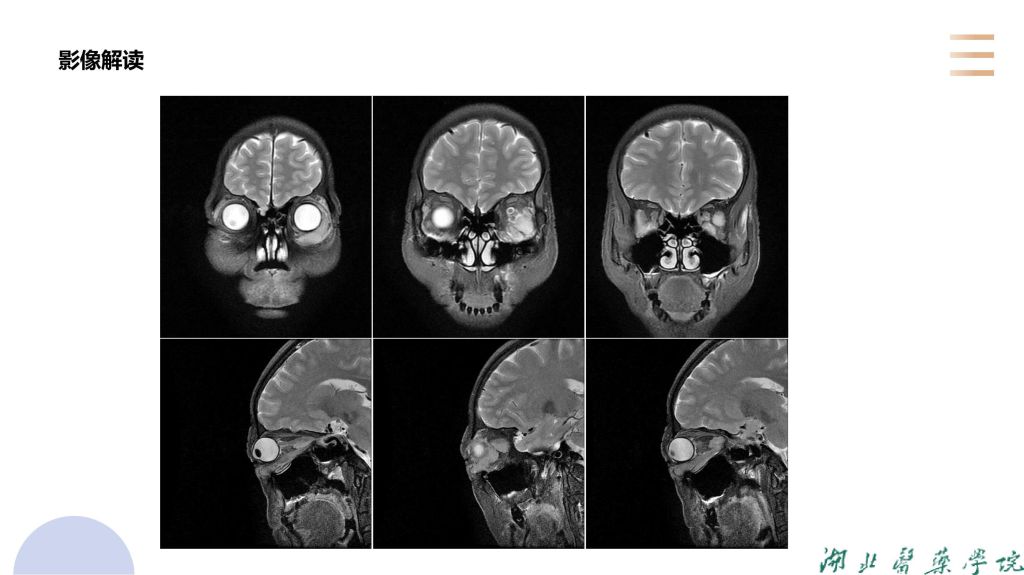

病例分析-眼眶淋巴瘤